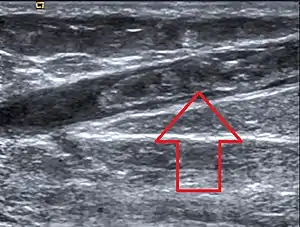

Em presença de um paciente com sinais e sintomas sugestivos de tromboflebite deve ser efectuado em urgência um ecodoppler venoso dos membros inferiores.[1]